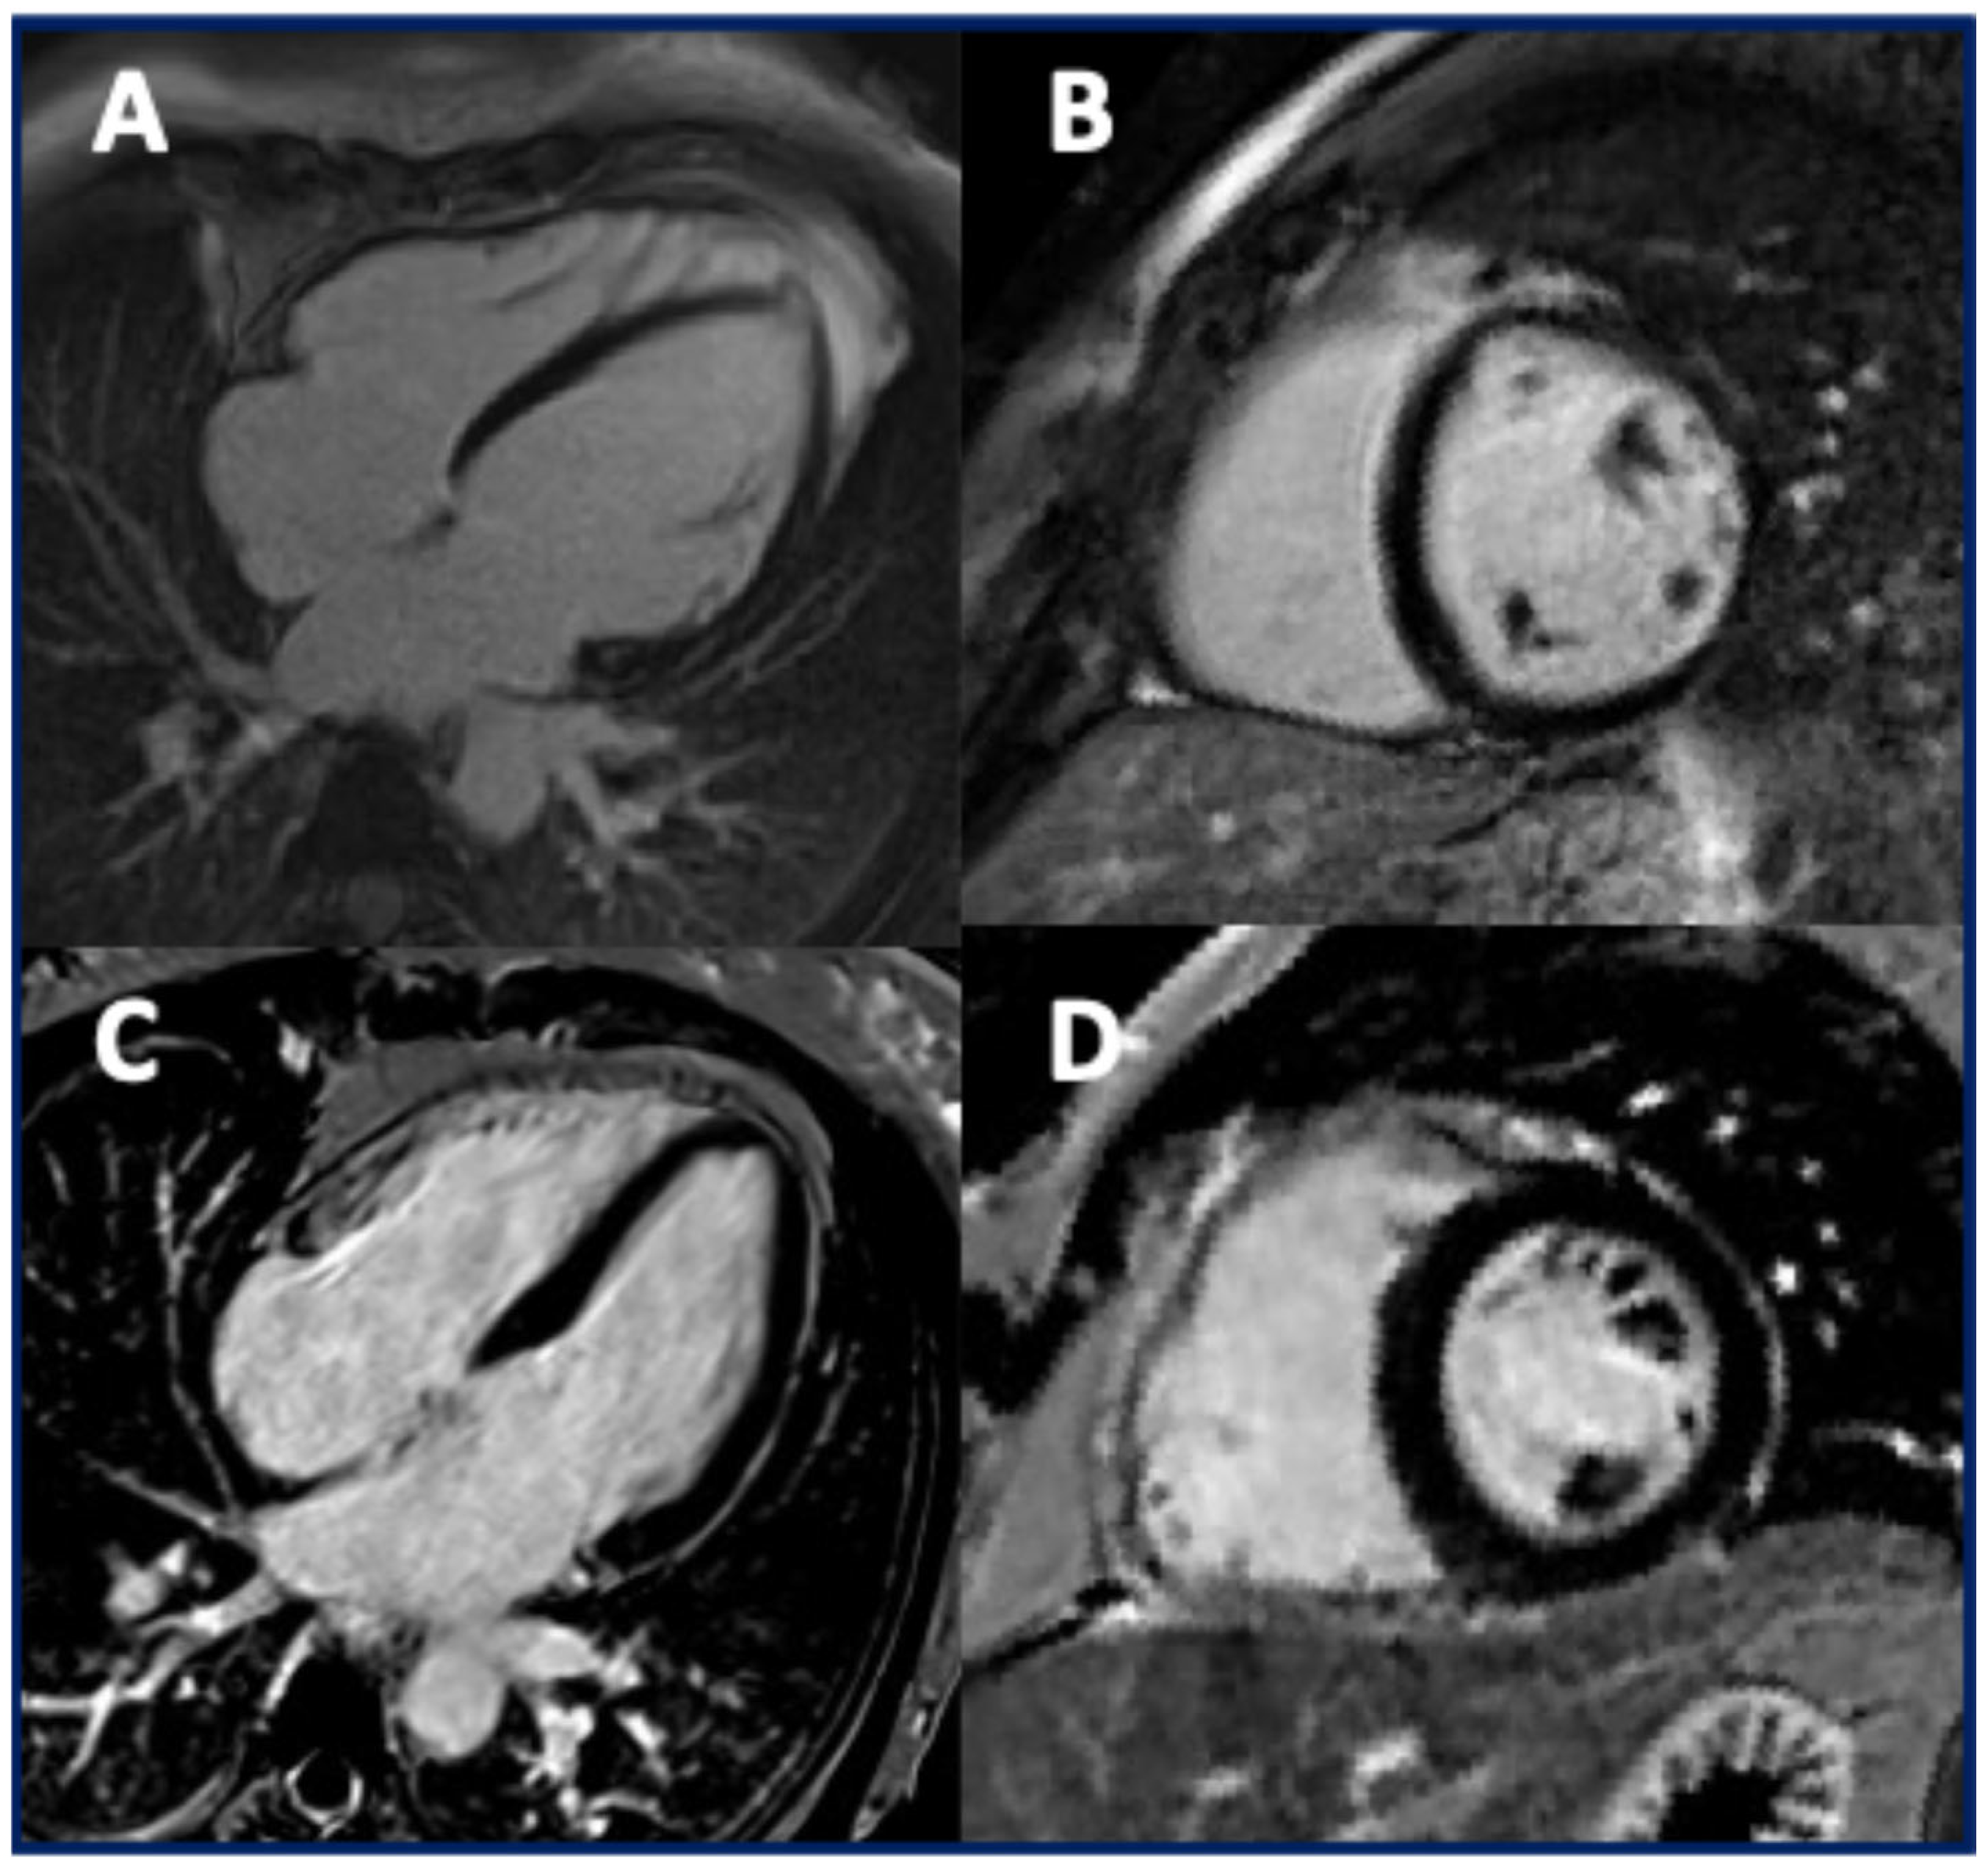

3.4. The Imaging Features of Patients with TMEM43 Cardiomyopathy

4.3. The Imaging Findings in Patients with TMEM43 Cardiomyopathy

| Matos J, Radiol Cardiothorac Imaging 2023 [15] | To describe the CMR findings in ARVC patients with TMEM43 pathogenic or VUS variants using the 2020 Padua Criteria | 14 ARVC pts with a pathogenic variant (n = 8) and a VUS (n = 7) of TMEM43 | c.1073C>T and other VUS | p.Ser458Leu and other | TMEM43-related ARVC shows progressive LV dysfunction and subepicardial fibrosis, requiring longitudinal clinical and imaging follow-up. |